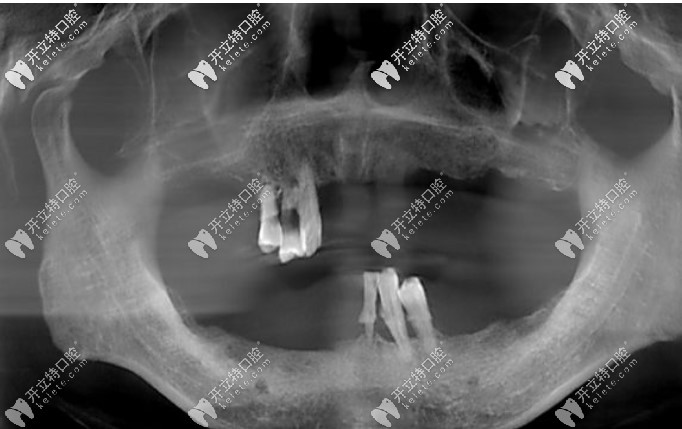

從小到大,我的牙齒中線不齊,咬合也有問(wèn)題,沒(méi)想過(guò)中線不齊及咬合不好會(huì)造成臉歪等影響,只是覺(jué)得擁有滿口整齊大白牙的人笑起來(lái)都非常好看,但自己卻只能抿嘴笑,因?yàn)榭傆X(jué)得自己的牙齒不好看。

整牙前牙齒中線不齊咬合不良